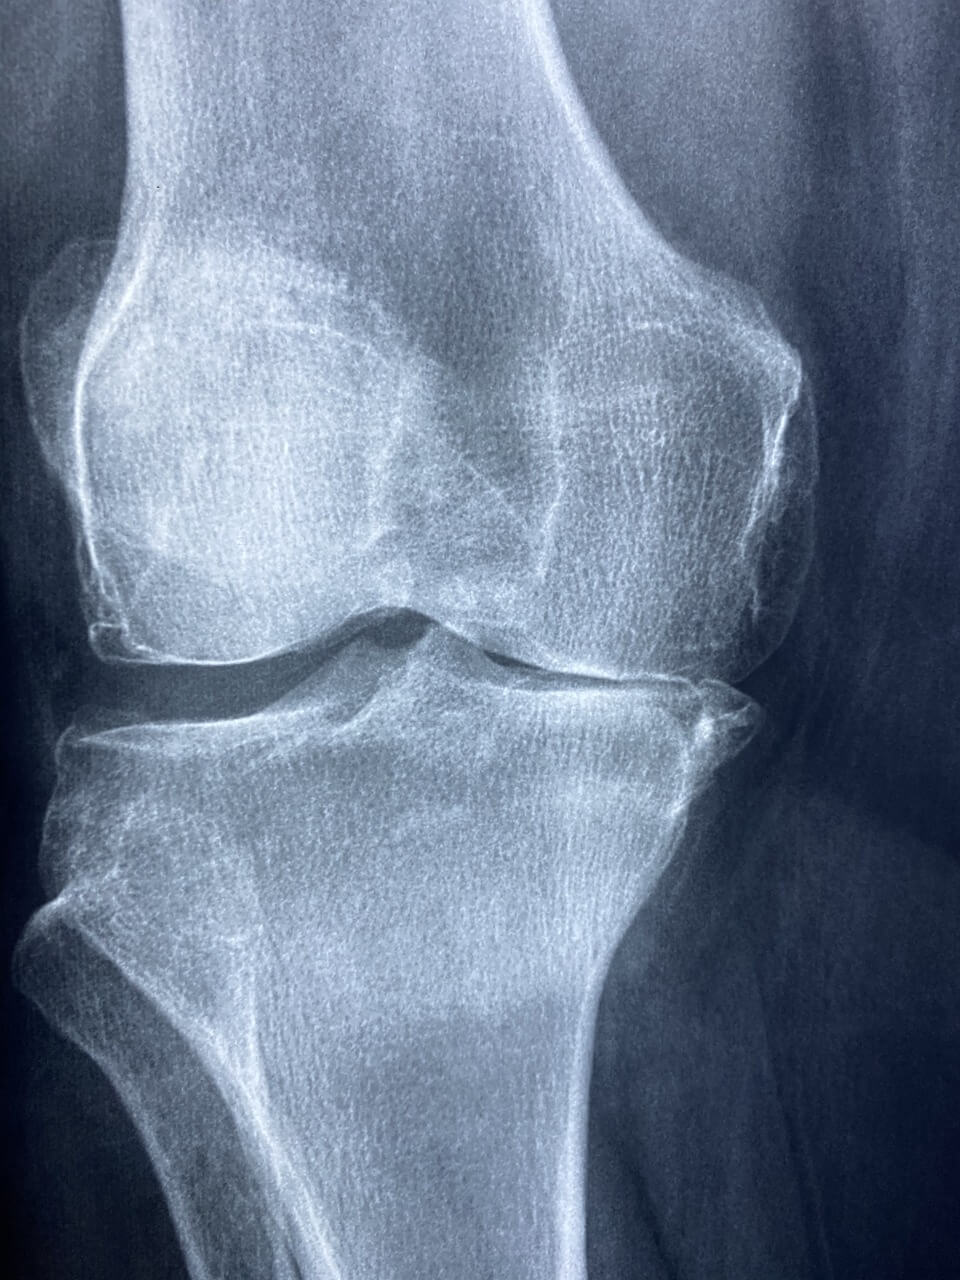

골다공증 초기증상은 눈에 잘 띄지 않아 많은 이들이 놓치기 쉽습니다. 뼈는 겉으로 드러나지 않지만 조용히 약해지고 있습니다. 사소한 허리 통증이나 무릎 불편감도 골다공증 초기증상일 수 있습니다.

등이 구부정해지고 키가 줄어든 느낌, 무거운 물건을 들었을 때 갑자기 느껴지는 요통 등은 골다공증 초기증상으로 나타나는 주요 징후입니다.

골다공증 초기증상은 시간이 지날수록 점점 심해지며, 작은 충격에도 골절이 일어날 수 있는 상태로 이어지기 때문에 조기 발견이 무엇보다 중요합니다.